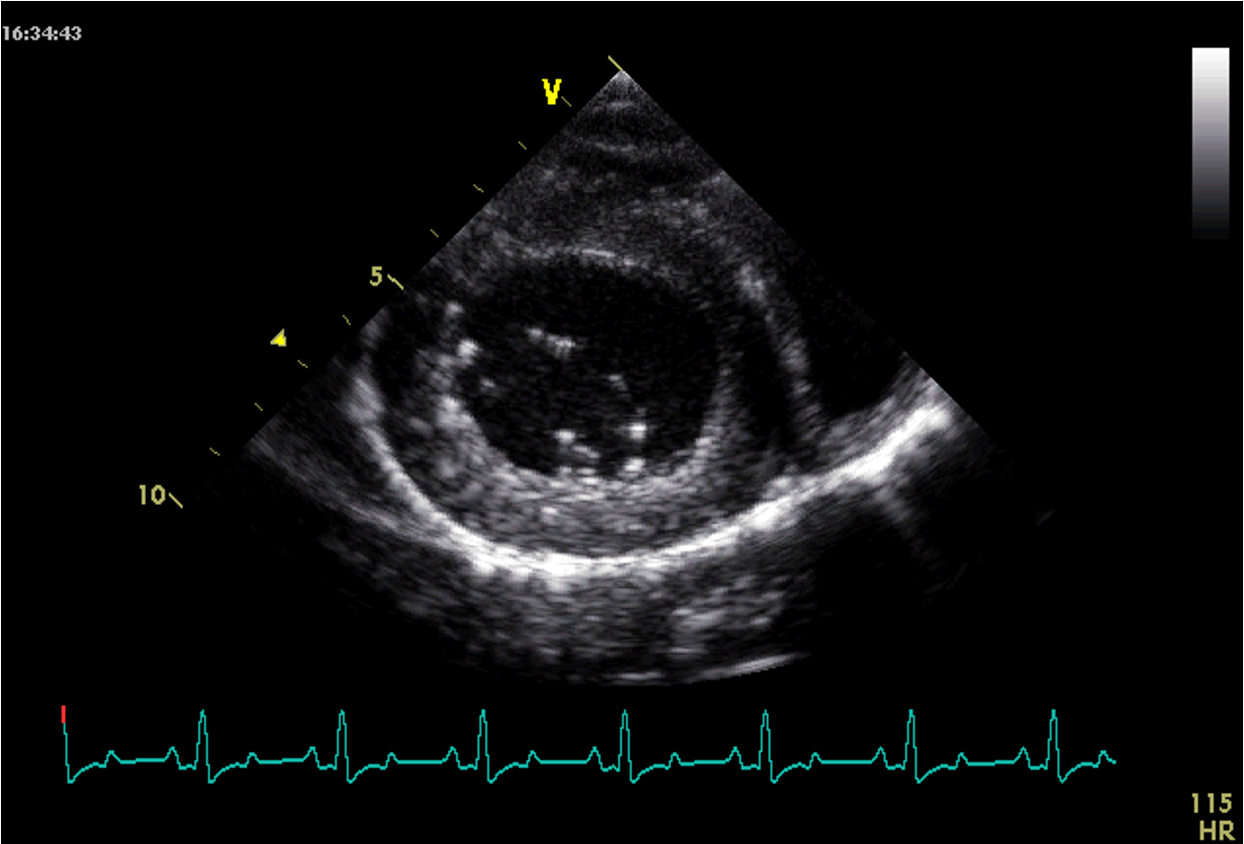

Which view is this?

Right parasternal short axis view LV @ pap mm level

Right ventricle small at the top.

Left ventricle dominating in the middle.

PAP = Elevated pulmonary pressure (PAP) -> attach doppler in this view

MM = measure left ventricle